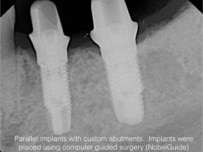

When we make crowns, the back teeth are just as important as the front teeth when it comes to aesthetics.  What is especially important is making sure the gum tissues surrounding your crowns are totally healthy on a long term basis.  This is accomplished by controlling the contours (emergence profile) as your final restoration is created.  The following slide sequence demonstrates computer guided implant placement, custom abutments, metal free crowns, and a long term successful outcome.